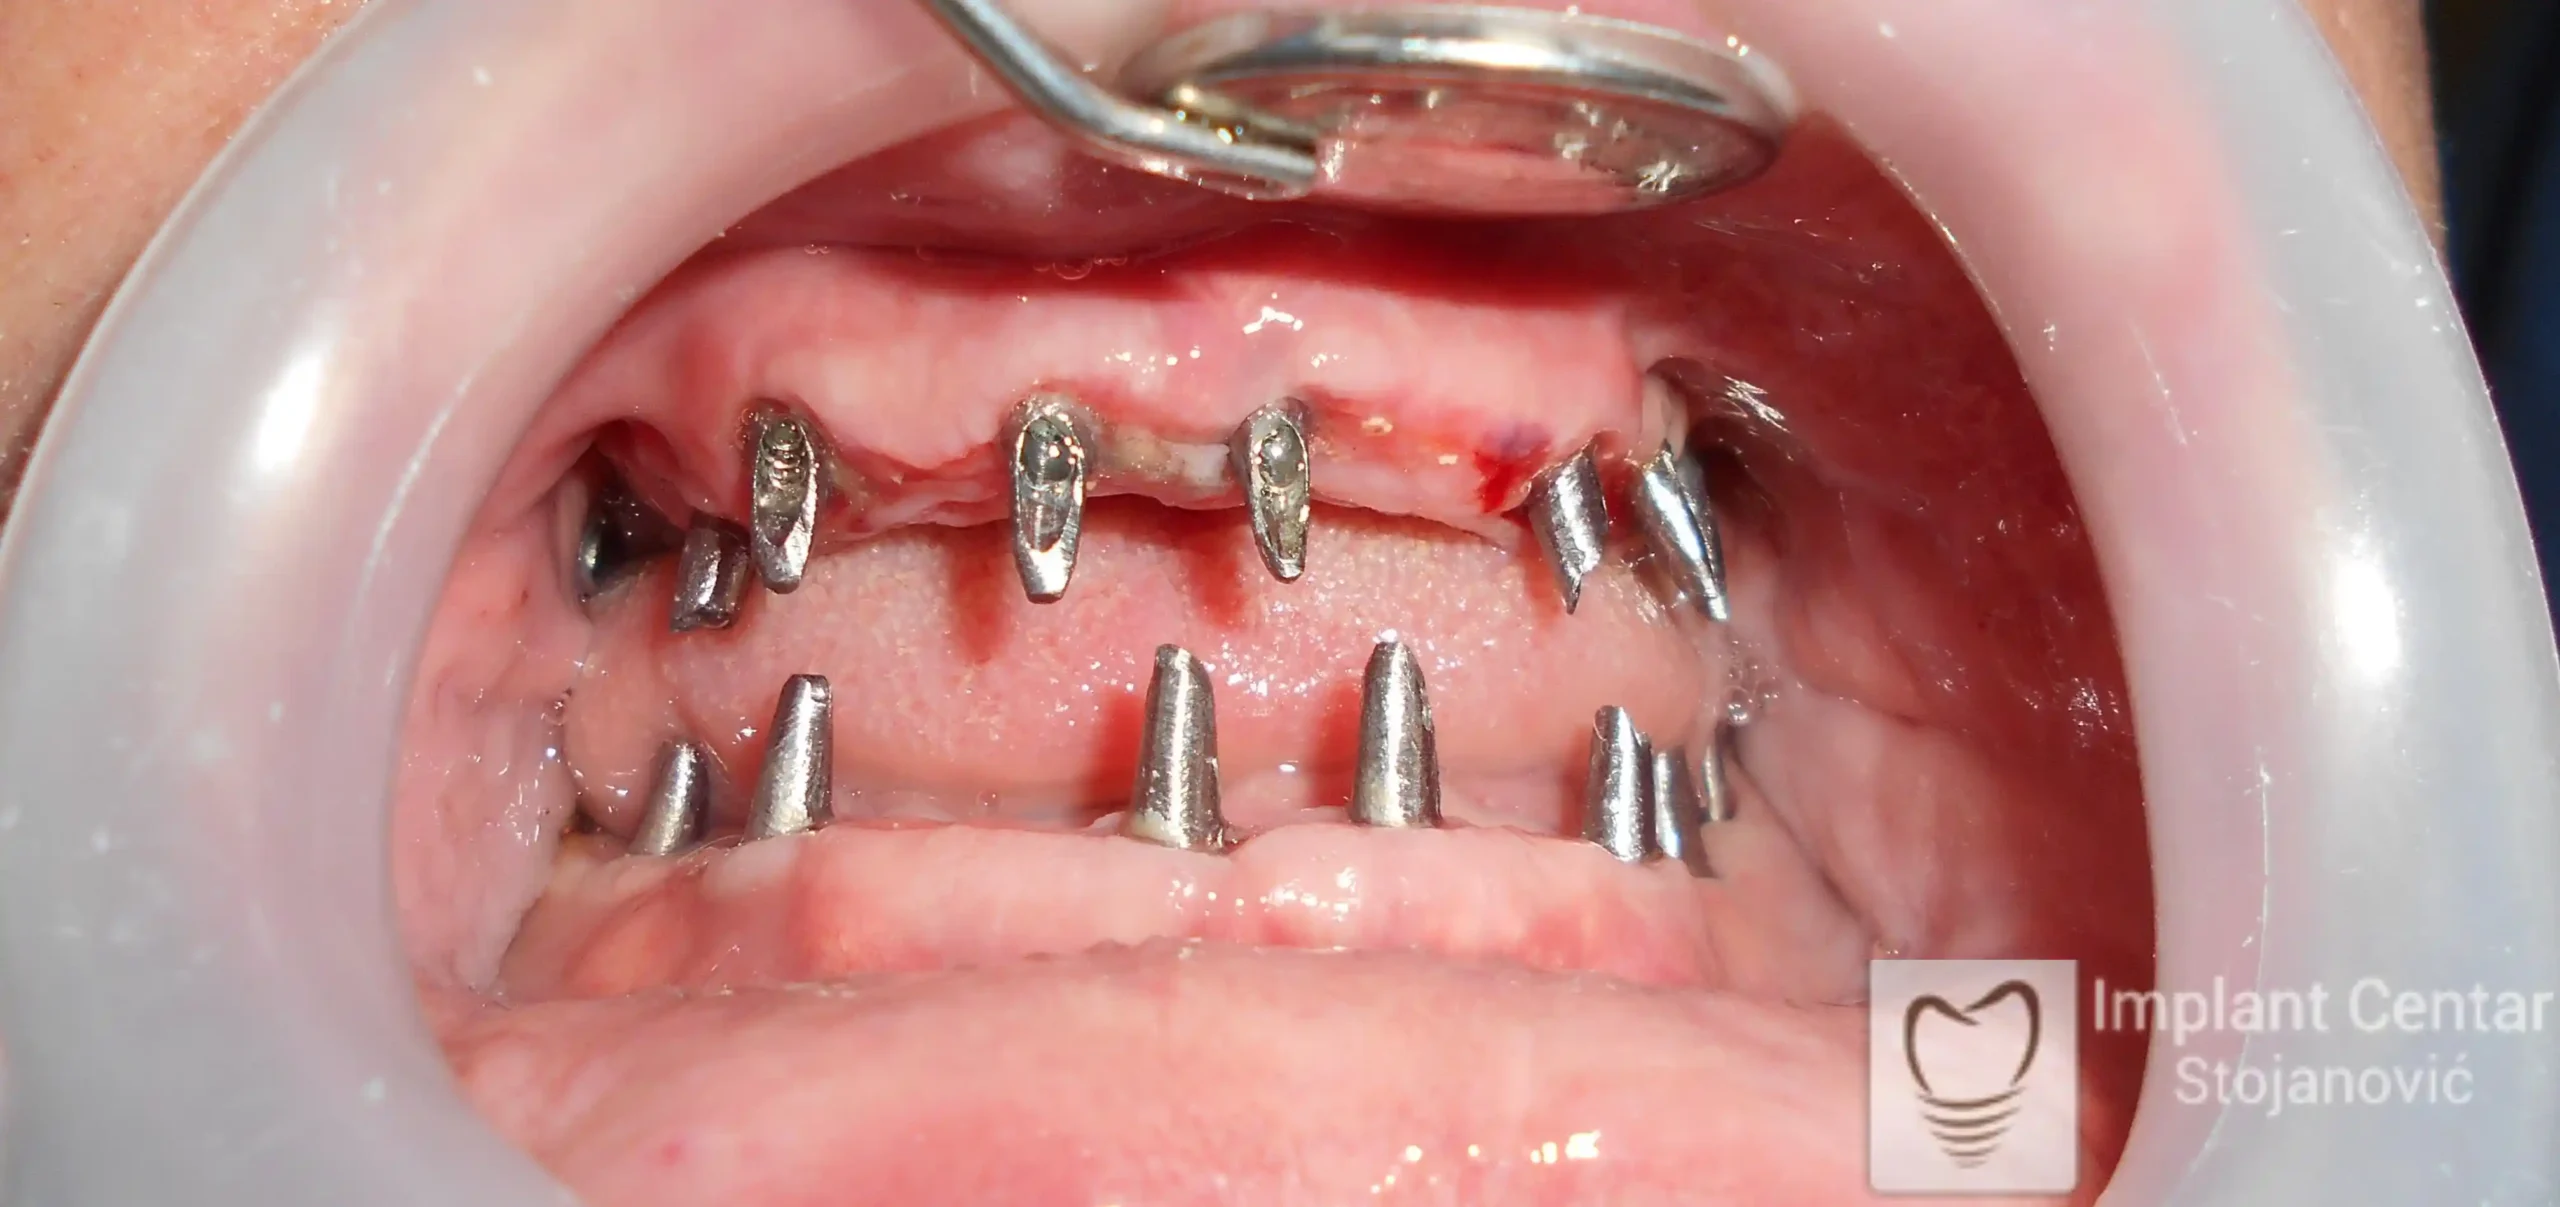

Pacijent sa rascepom usne, nepca i alveolarnog grebena uspešno je rehabilitovan fiksnim protetskim radom na implantatima. Pre dolaska u našu ordinaciju, pacijent je u gornjoj vilici nosio totalnu protezu preko preostalih zuba, dok je u donjoj vilici bio zbrinut parcijalnom mobilnom protezom. Tokom višegodišnje potrage za adekvatnim rešenjem, pacijent nije uspeo da pronađe zadovoljavajuću terapijsku opciju ni u zemlji ni u inostranstvu.

Nakon detaljnog kliničkog pregleda i analize radioloških snimaka, izrađen je sveobuhvatan plan terapije sa ciljem uklanjanja mobilnih proteza i postizanja maksimalne funkcionalne i estetske rehabilitacije. Zbog loše biološke vrednosti preostalih zuba, doneta je odluka o njihovom vađenju i ugradnji dentalnih implantata.

Poseban terapijski izazov predstavljalo je premošćavanje defekta nastalog usled rascepa, kao i ograničena količina raspoložive kosti u gornjoj vilici. Primenom većeg broja implantata i odgovarajućih procedura nadoknade kosti, postignuta je stabilna osnova za fiksni protetski rad.

Tokom perioda oseointegracije, pacijent je bio zbrinut fiksnim privremenim krunicama, čime je već pet dana nakon intervencije obezbeđena potpuna funkcionalna i estetska rehabilitacija. Nakon završetka perioda integracije implantata, izrađeni su definitivni cirkonijum-keramički mostovi na implantatima.